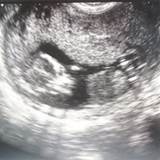

妊娠4ヶ月のエコー検査では、赤ちゃんの頭が向かって左側にあることがはっきりわかりました。

超音波の画面を見ていると右下がポコポコ動いていました。先生によると、ポコポコしている部分は心臓だそうです。まだ経膣エコーなので不快感が少し残りますが、今回は赤ちゃんの成長がよくわかったので良かったです。ゆりさん自身も母親の実感をさらに強く感じた検査でした。

来月からはお腹の上からのエコー検査に切り替わるそうです。経膣エコーは苦手なので、ちょっと安心しました。まだ性別はわかりませんが、妊娠6ヶ月以降にわかるかもしれないとのことでした。